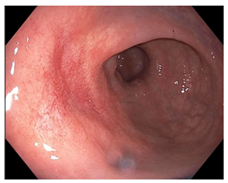

| Endoscopy | Flat white scar Telangiectasia Absence of ulcers and mucosal nodularity | Small mucosal nodules/minor mucosal irregularities Superficial ulceration Mild, persistent erythema of the scar | Visible tumor |

| Small mucosal nodules, minor mucosal irregularities | ![]() | ![]() | ![]() |

| Persisting erythema of scar | ![]() | ![]() | ![]() |